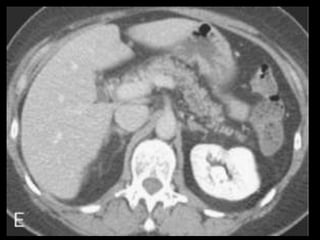

A administração de contraste IV é essencial,

especialmente em pacientes com PA grave, para

visualizar o pâncreas, diferenciar a glândula de

coleções líquidas adjacentes e do tecido

inflamatório peripancreático e demonstrar a

necrose pancreática.

Áreas focais ou difusas de realce diminuídas ou

ausente à TC contrastada dinâmica constituem

áreas de isquemia ou necrose.

TC tem precisão geral de 87% com S e E de 100%

para necrose extensa e 50% com áreas menores.